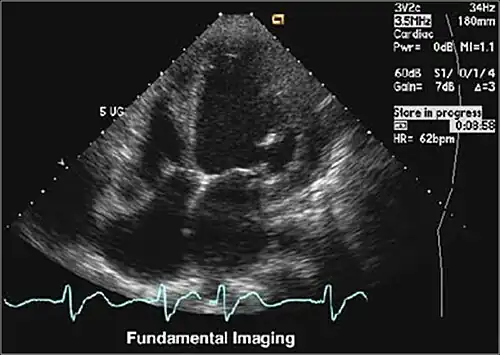

Tissue Harmonic Imaging

Tissue Harmonic Imaging (THI) ist ein Verfahren in der medizinischen Ultraschallbildgebung, das vor allem die Kontrastauflösung, aber auch die räumliche Auflösung erhöht. Grundsätzlich wird dabei Ultraschall mit einer Frequenz („Grundwelle“ oder „1. Harmonische“) in das Gewebe gesendet und die Signale mit der doppelten Frequenz, also („Oberwelle“ oder „2. Harmonische“) für die Bildgebung verwendet, die durch die nichtlineare Ausbreitung im Gewebe entstehen.

Häufig ist das Fettgewebe an der Körperoberfläche die Ursache für störende Artefakte. Da die Oberwellen erst mit der Ausbreitung im Gewebe zunehmen, sind Bilder, die aus diesen Frequenzen erstellt werden, frei von diesen Artefakten. Darüber hinaus ist die räumliche Auflösung höher, weil die Frequenz höher ist.